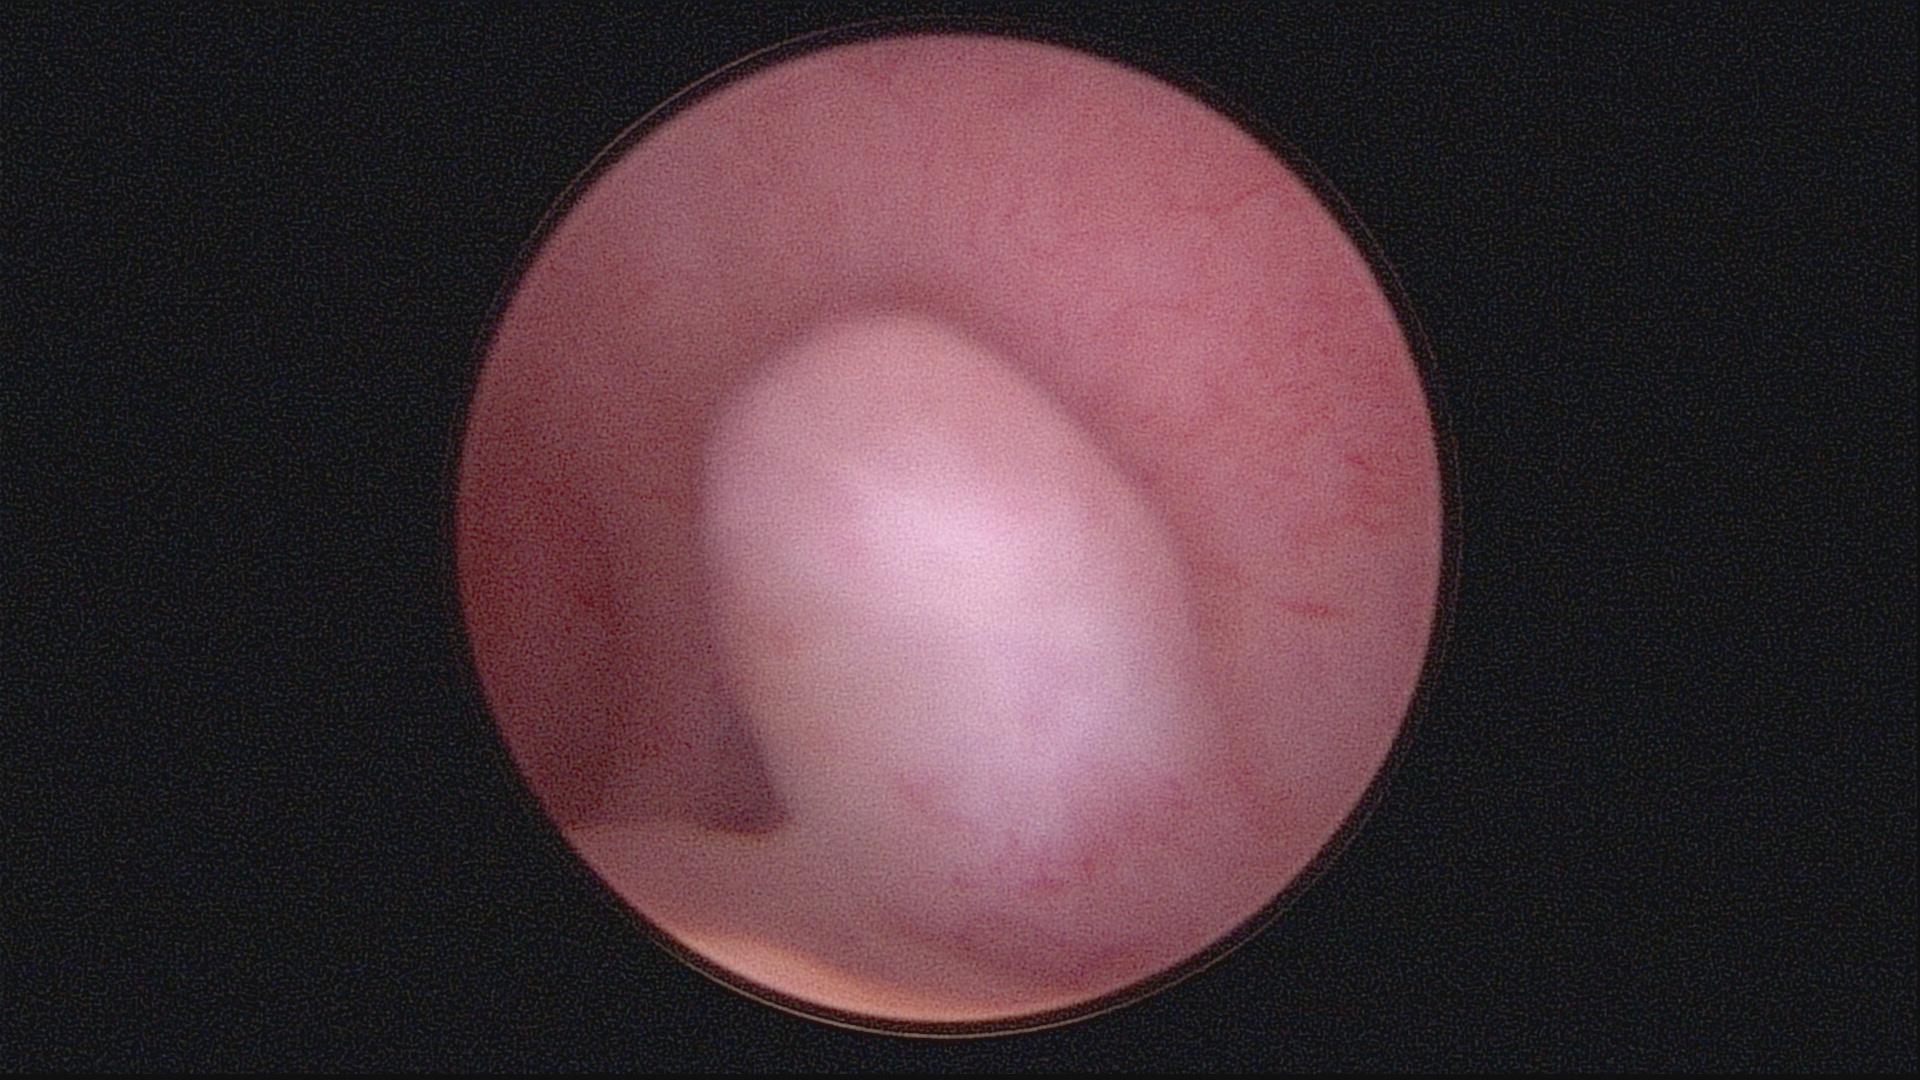

图二:整复好的宫腔